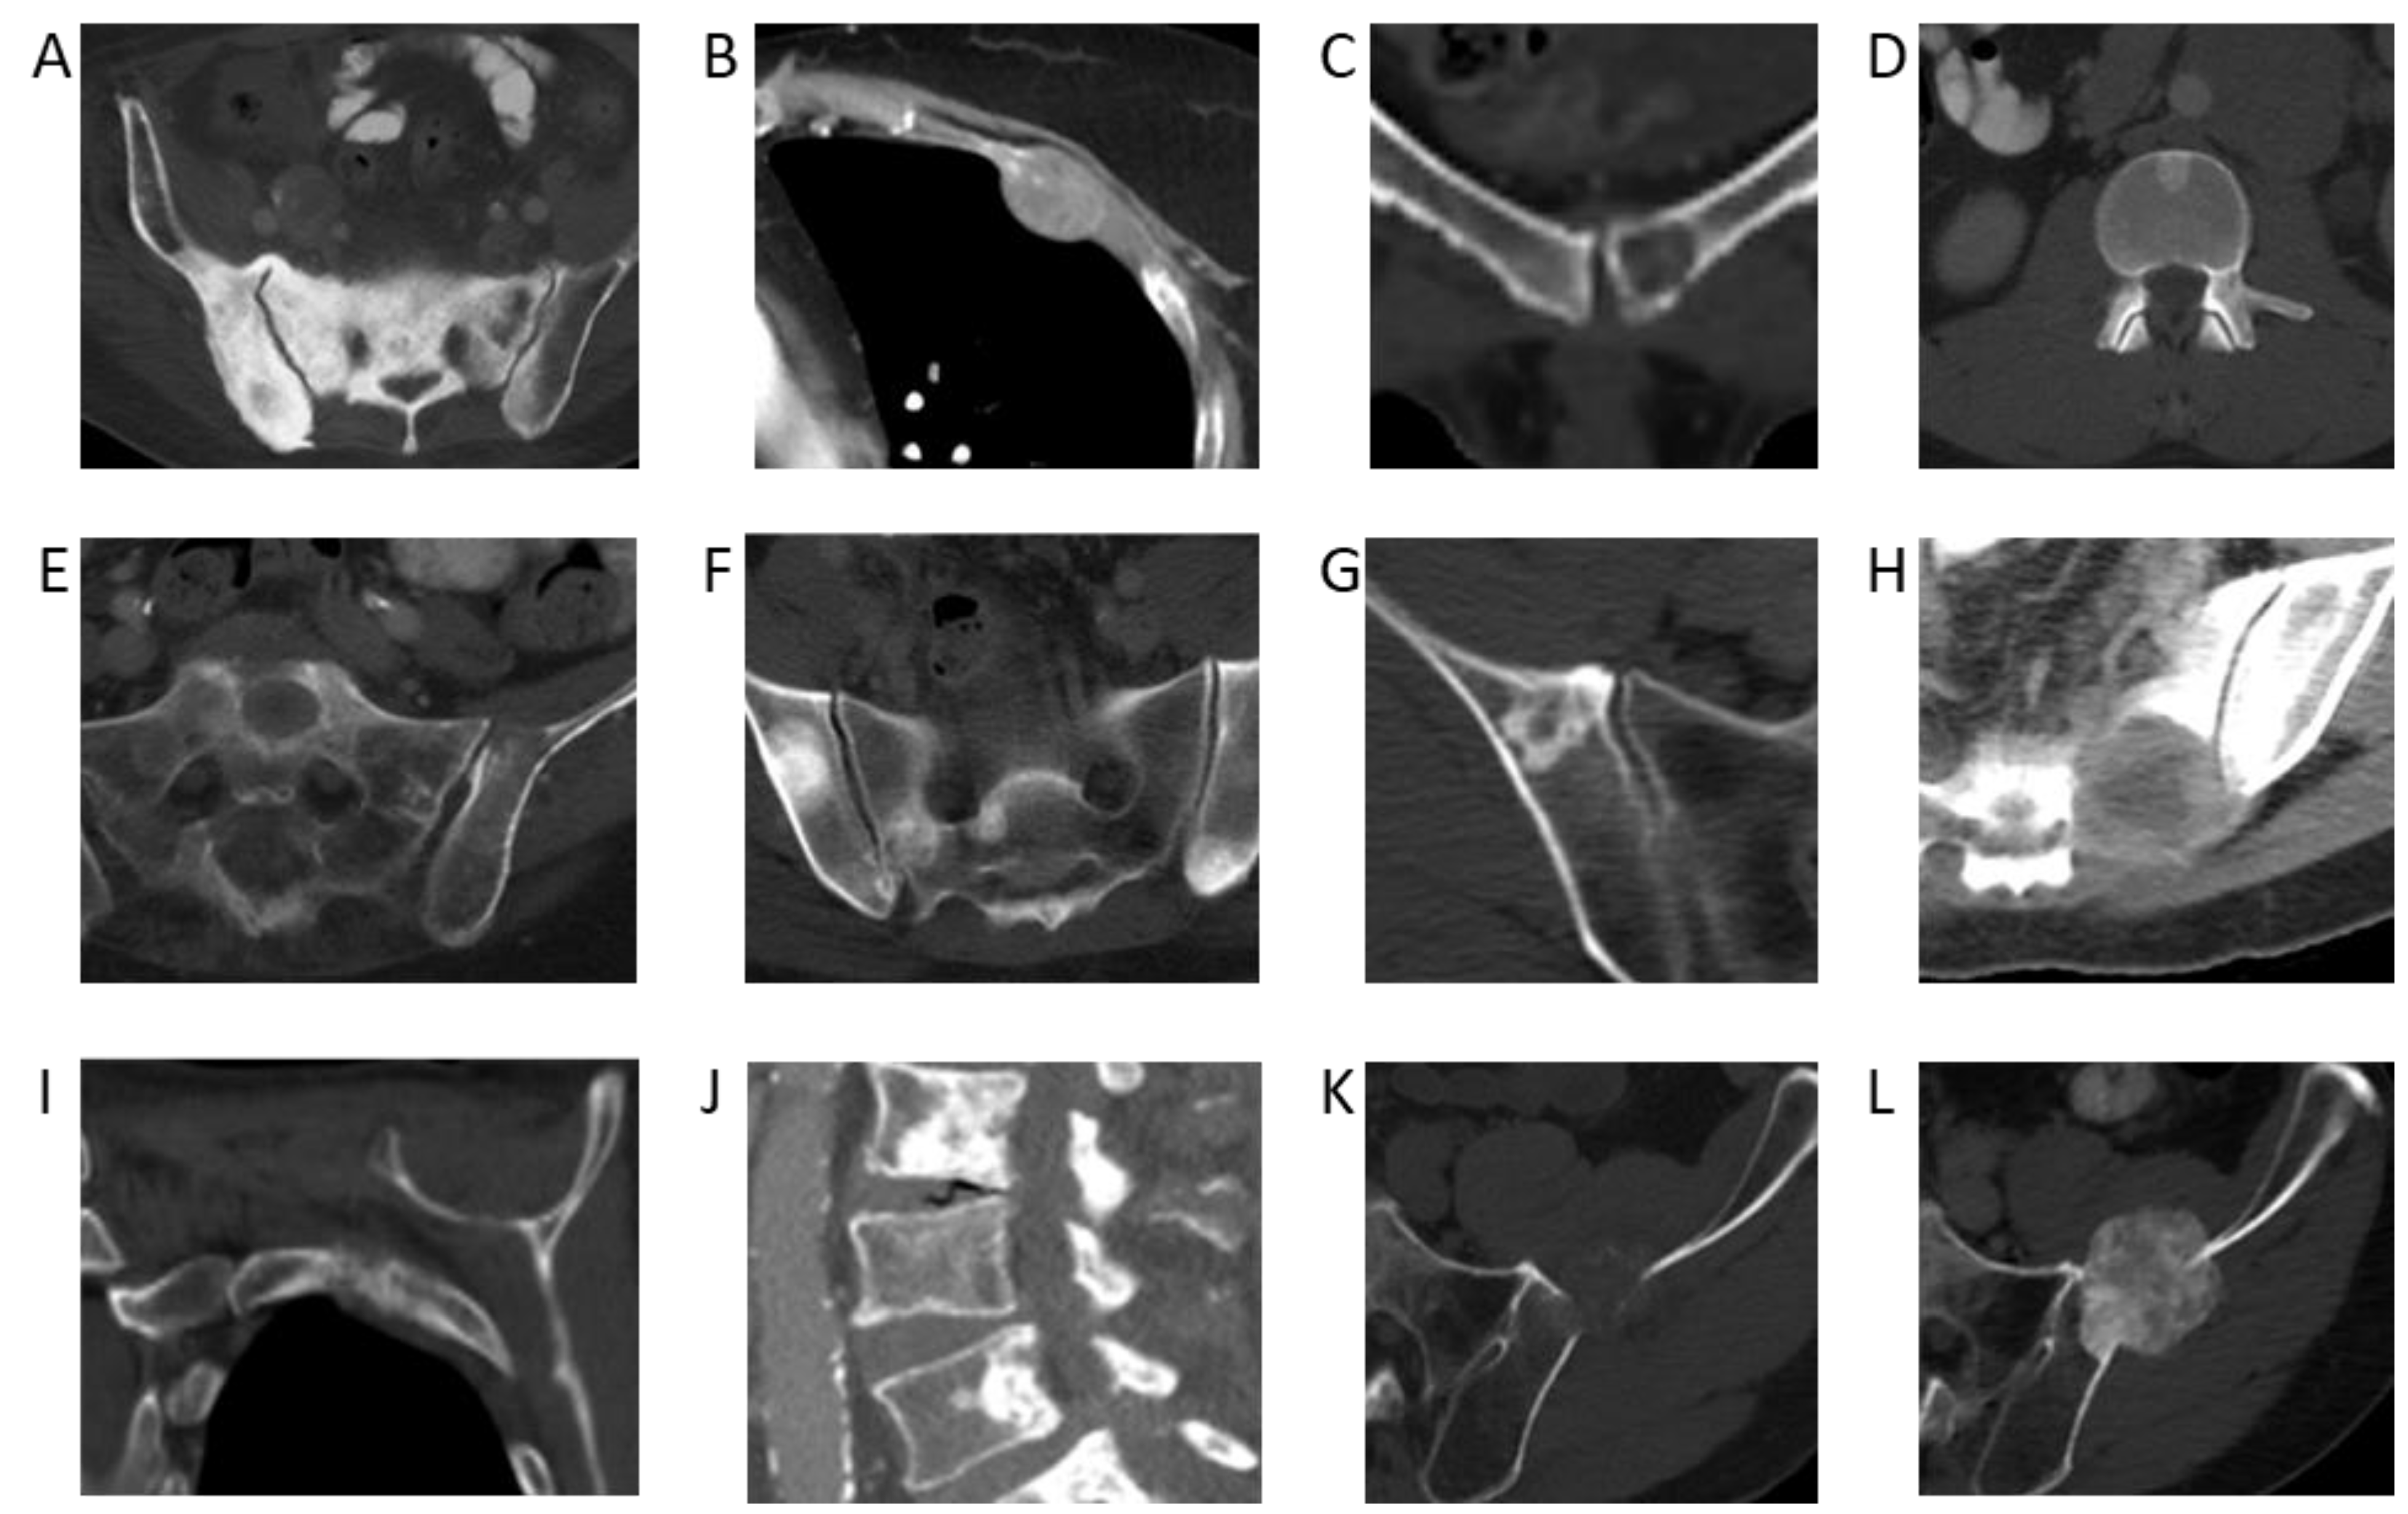

Using the NLP model, the cancer with the highest 5-year incidence rate of bone metastases was prostate cancer, with an incident rate of 52% (95% confidence interval [CI]: 50–54%). This was followed by breast cancer, with an incident rate of 41% (95% CI: 39–42%), head and neck cancer, with an incidence rate of 36% (95% CI: 32–40%), and lung cancer, with an incidence rate of 33% (95% CI: 32–34%) (Table 1). Incidence rates of bone metastases across melanoma, hepatobiliary, pancreatic, and esophageal cancers were also high (from 20–30%). Examples of CT images from cancers with a high incidence rate of bone metastases are shown in Figure 2.

Incidence rates of bone metastases across colorectal, ovarian, genitourinary, and gastric cancers were low (from 10–20%). The lowest incidence rates were found in central nervous system cancer, with an incident rate of 8% (95% CI: 4–11%) and testicular cancer, with an incident rate of 5% (95% CI: 4–6%). Examples of CT images from cancers with a low incidence rate of bone metastases are shown in Figure 3. Prior studies based on autopsy data report higher incidences of bone metastases in breast (67% vs. 41%), prostate (66 vs. 52%), and lung cancer (36 vs. 33%) [8]. This discrepancy can possibly be explained by the fact that patients in our study were evaluated at earlier time points in their cancer journey, whereas autopsy studies are evaluated only once patients have succumbed to their cancer. On the other hand, autopsy studies have reported lower incidences of bone metastases than our NLP-derived results for colorectal cancer (11% vs. 16%) [9,10] and ovarian cancer (9% vs. 11%) [9]. This may be partially attributable to advances in treatment options and associated increased survival, with more patients today living long enough to develop bone metastases. For example, with the introduction of adjuvant treatment regimens, the median survival of patients with advanced colorectal cancer has increased to more than 20 months, with a corresponding increase in the likelihood of developing bone metastases and having adverse skeletal-related events [9,10,11,12,13,14]. The utilization of NLP to extract information from routine CT staging scans affords us the ability to better evaluate the temporal development of bone metastases during a patient’s cancer journey.

Figure 2. Bone metastases from primary cancers with the highest incidence rates. (A) Sclerotic pelvic metastases in a 76-year-old male patient with prostate cancer. (B) Lytic metastasis in the left third rib in a 60-year-old female patient with breast cancer. (C) Lytic metastasis left pubic bone in a 48-year-old female patient with thyroid cancer. (D) Sclerotic metastasis in an L1 vertebral body in a 59-year-old male patient with adenoid cystic carcinoma of the tongue. (E) Lytic metastases in the left sacral ala and left ilium in a 65-year-old male patient with poorly differentiated lung adenocarcinoma. (F) Multiple sclerotic pelvic bone metastases in a 57-year-old male with a lung carcinoid tumor. (G) Sclerotic right iliac metastasis in a 63-year-old female patient with melanoma. (H) Lytic left sacral metastasis in a 55-year-old female patient with melanoma. (I) Lytic left second rib metastasis in a 60-year-old female patient with hepatocellular carcinoma. (J) Multiple lumbar spine sclerotic metastases in a 92-year-old male patient with hepatocellular carcinoma. (K) Lytic left iliac metastasis in a 67-year-old male patient with esophageal cancer. (L) Follow-up demonstrating interval sclerosis of the left iliac metastasis representing treatment effect.

Figure 3. Bone metastases from primary cancers with the highest incidence rates. (A) Sclerotic pelvic metastases in a 76-year-old male patient with prostate cancer. (B) Left 5th rib lytic metastasis in an 84-year-old male with colorectal cancer. (C) Lytic metastasis T5 vertebra in a 64-year-old female patient with ovarian cancer. (D) Sclerotic metastasis right acetabulum in a 62-year-old male patient with urothelial cancer. (E) Lytic metastasis left ilium in a 54-year-old female patient with renal cell cancer. (F) Lytic metastasis left ilium in a 44-year-old male patient with renal cell carcinoma. (G) Multiple sclerotic lumbar spine metastases in a 54-year-old male patient with urothelial carcinoma of the renal pelvis. (H) Sagittal CT lumbar spine of multifocal sclerotic osseous metastases in a 35-year-old female patient with HER2-negative gastric cancer.